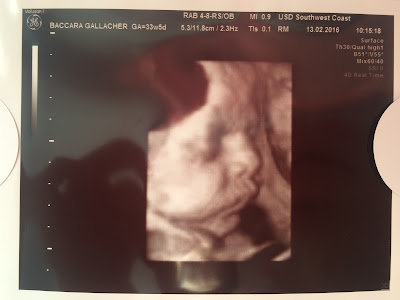

OUR 4D SCAN PHOTOS

As promised I thought I'd share the rest of the scan photos from our 4D Growth Scan. By NHS dates I was 33 weeks and 5 days on scan day although baby measured approx. 6lb 7oz and the scan report suggests I am about 20 days ahead of my dates. Only time will tell...